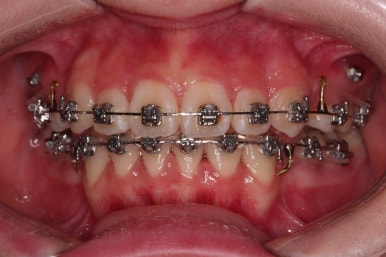

부산덧니교정 마무리를 한 모습인데요.

가지런한 모습 좋고, 교합이나 중앙선 등 매우 잘 맞네요.

전후를 비교해 볼게요.

치열, 교합, 악궁의 형태 매우 좋아졌어요.

다만 아직 어려서 카메라 사진을 찍을 때 어색해서 그런지 활짝 웃는 입술이 자연스럽진 않네요.

연습하면 충분히 좋아지고요.